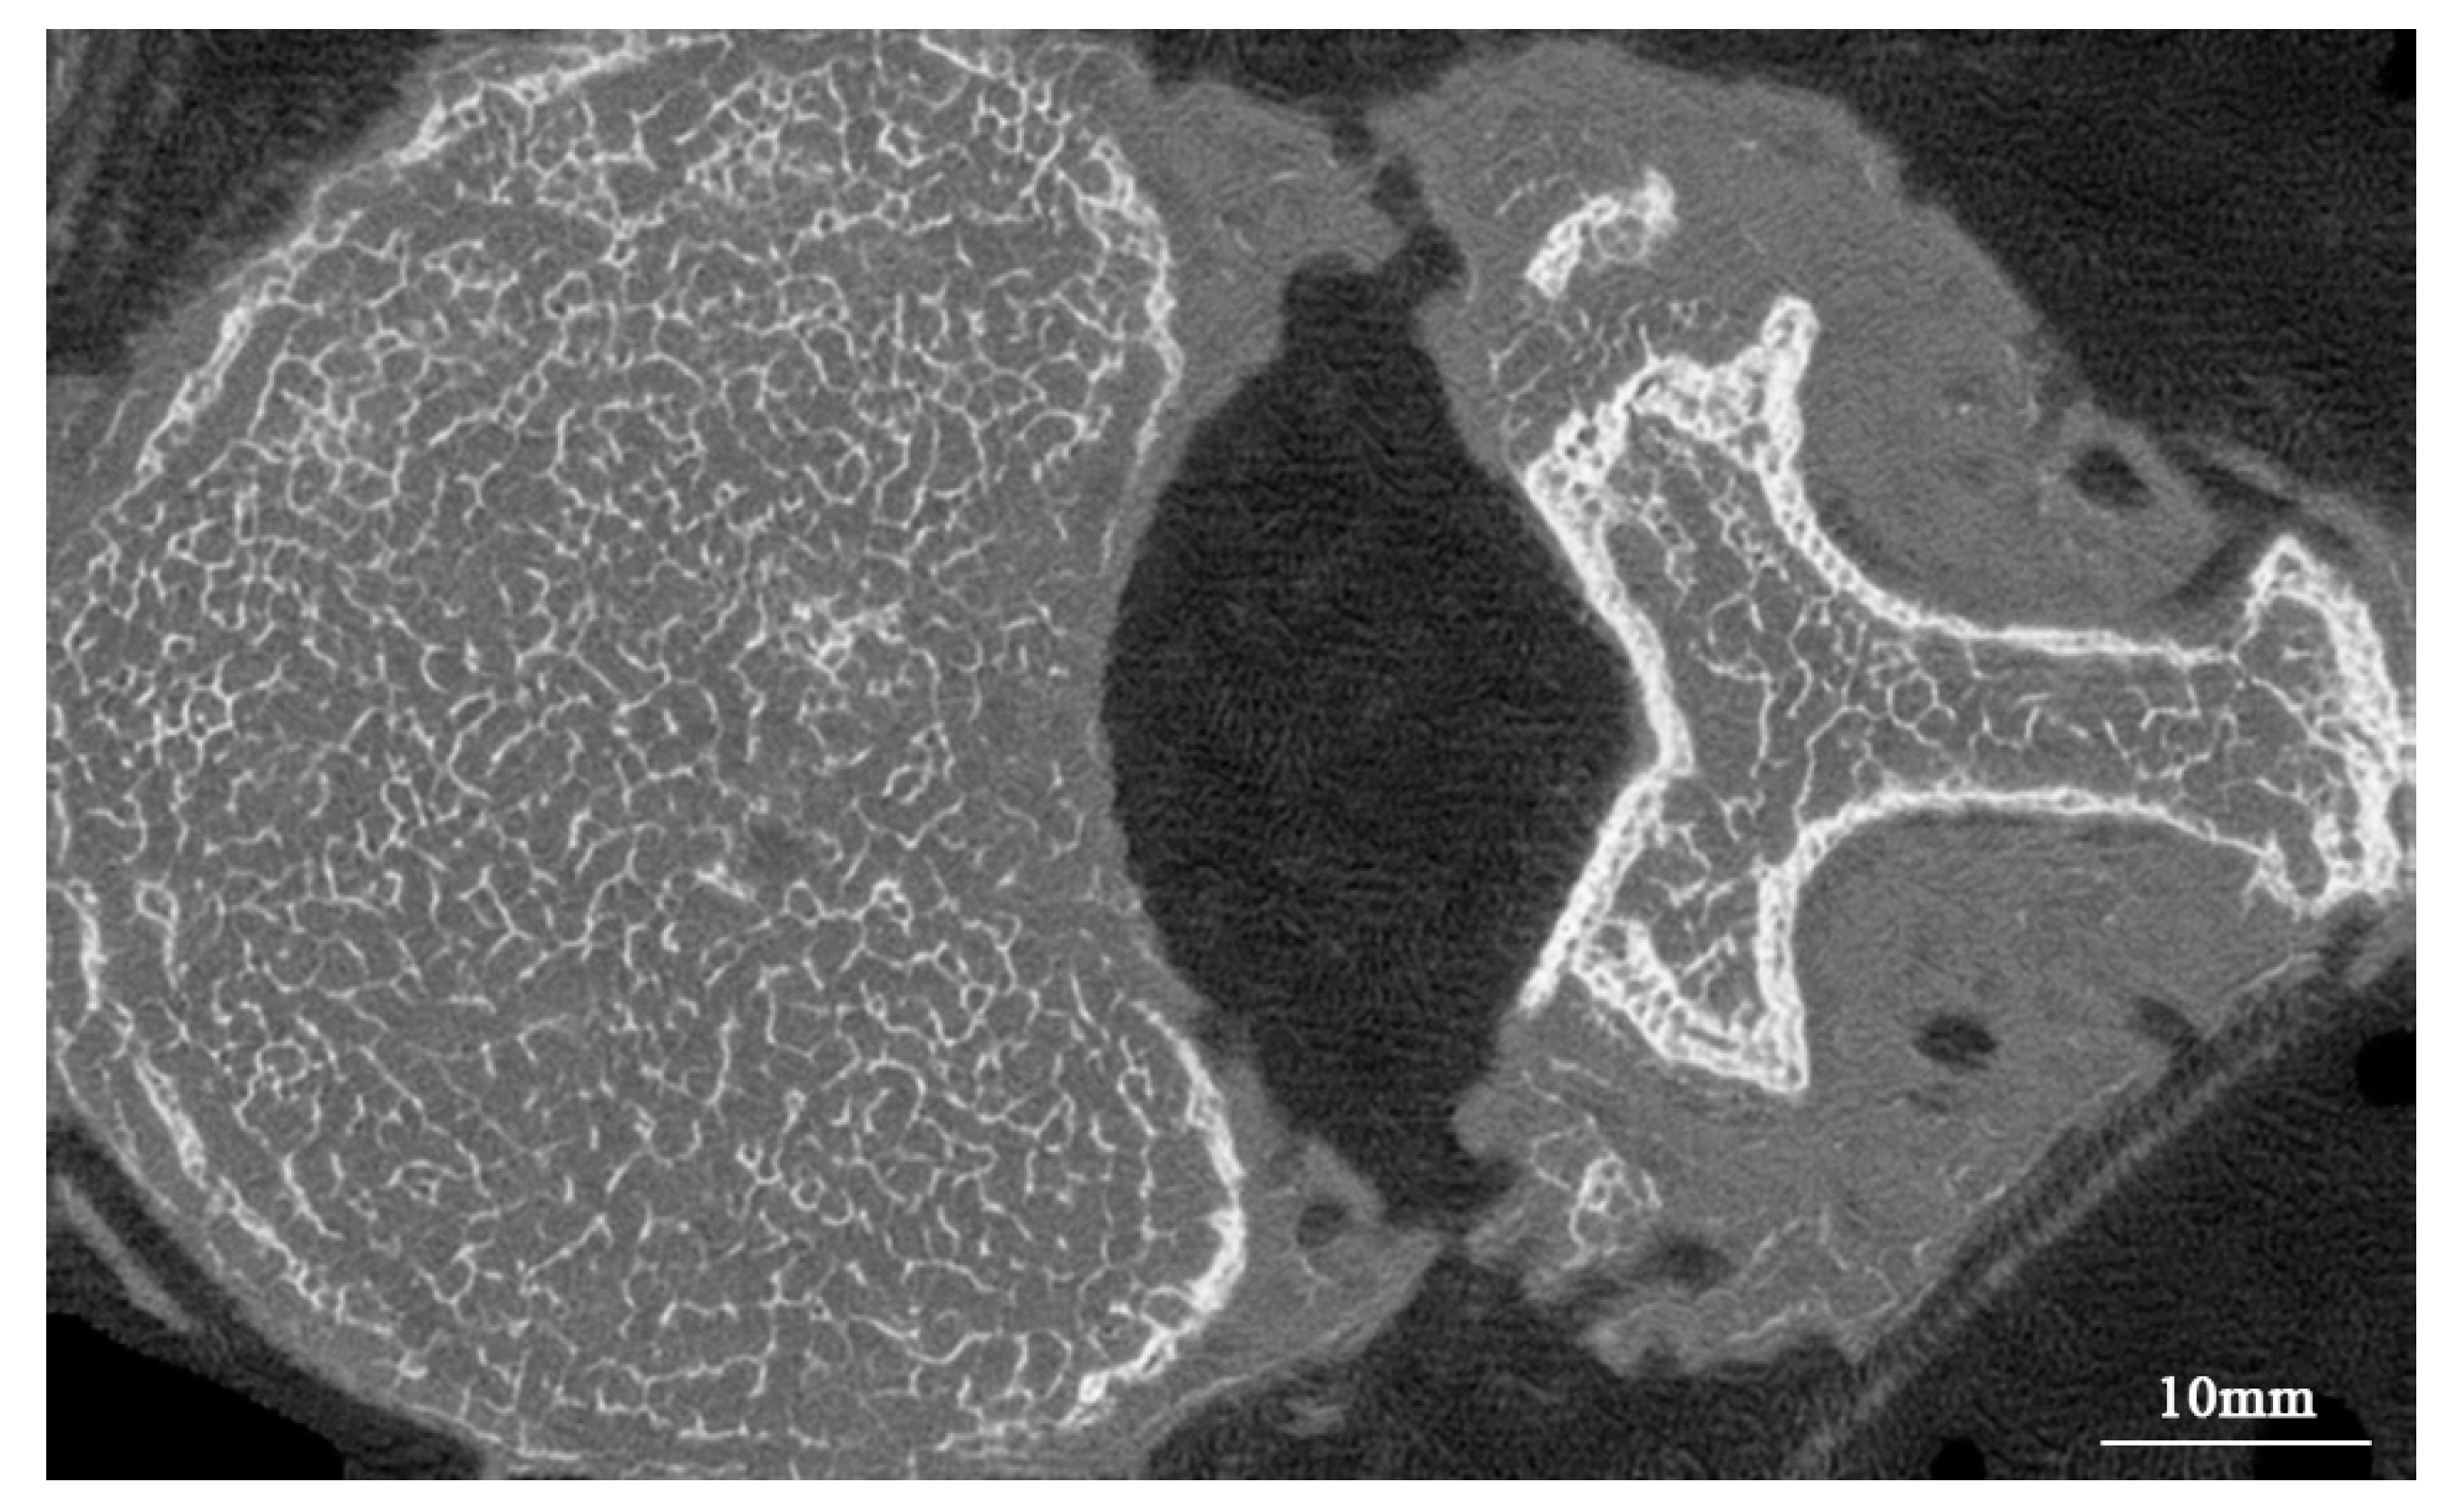

- Jin, D.; Zheng, H.; Zhao, Q.; Wang, C.; Zhang, M.; Yuan, H. Generation of vertebra micro-ct-like image from mdct: A deep-learning-based image enhancement approach. Tomography 2021, 7, 767–782. [Google Scholar] [CrossRef]